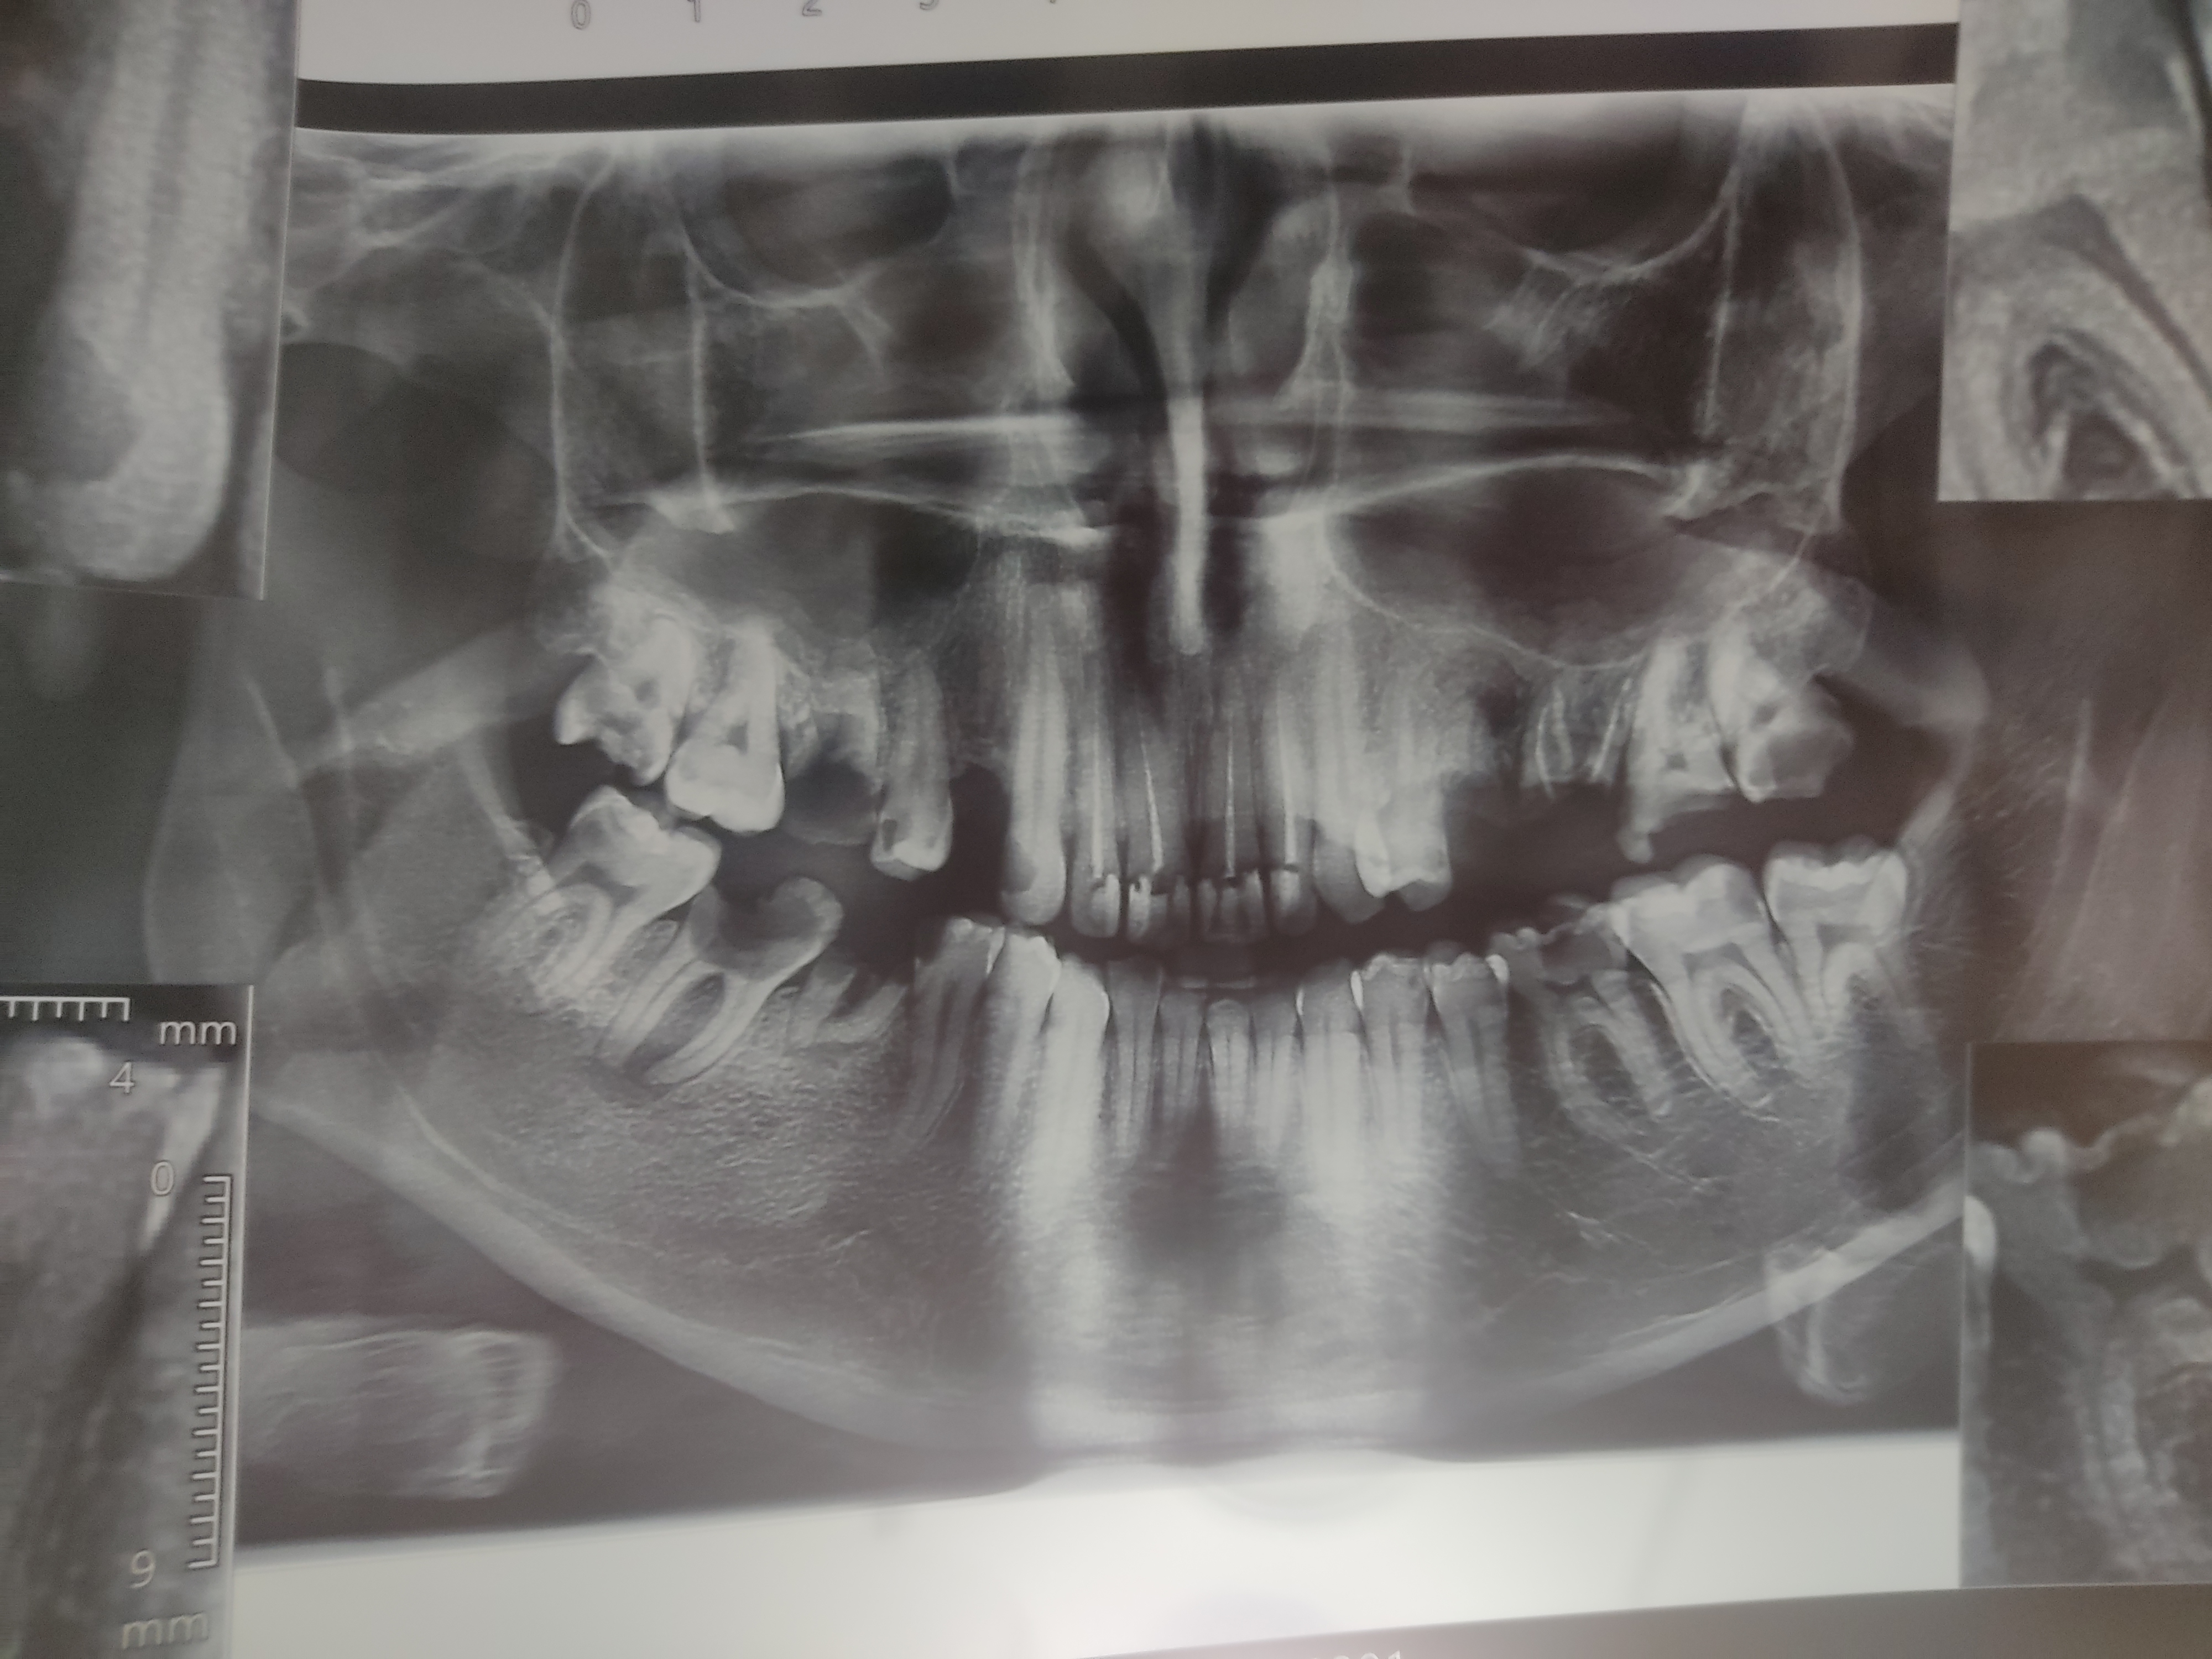

cactooos مدیر استارتر عضویت: 1402/09/24 تعداد پست: 2094 عنوان کسی از عکس دندون سر درمیاره opg 21 بازدید | 0 پست چند تاش نیاز به کشیدن داره ؟ میشه به روکش نگه داشت 1404/11/05 | 20:43 0 نفر لایک کرده اند ... گزارش تاپیک نامناسب